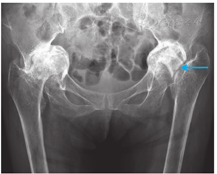

术后3个月随访,左髋关节屈曲80°、内旋20°、外旋30°;髋关节正位X线片示假体位置理想,人工股骨头位于臼杯内,股骨柄与骨质贴合良好,未见透光带(图4)。